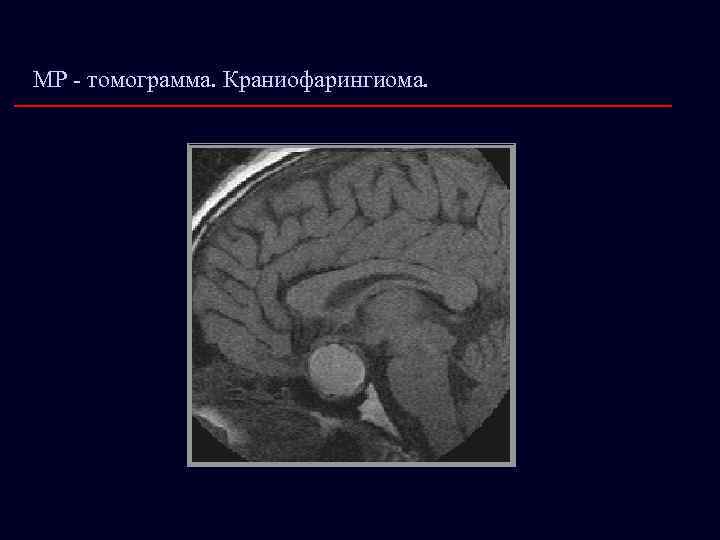

МР - томограмма. Краниофарингиома.

КРАНИОФАРИНГИОМА Локализация: üЭндо-(эндосупра)селлярная üСтебельная üВентрикулярная Клиническая симптоматика: üГипертензионно-гидроцефальный синдром üХиазмальный синдром üНесахарный диабет üПарциальный или тотальный гипопитуитаризм üПсихо-эмоциональные нарушения